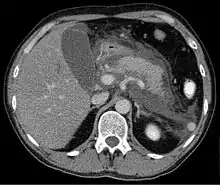

Computed tomography

Regarding the need for computed tomography, practice guidelines state:

CT is an important common initial assessment tool for acute pancreatitis. Imaging is indicated during the initial presentation if:

- the diagnosis of acute pancreatitis is uncertain

- there is abdominal distension and tenderness, fever >102, or leukocytosis

- there is a Ranson score > 3 or APACHE score > 8

- there is no improvement after 72 hours of conservative medical therapy

- there has been an acute change in status: fever, pain, or shock

CT is recommended as a delayed assessment tool in the following situations:

- acute change in status

- to determine therapeutic response after surgery or interventional radiologic procedure

- before discharge in patients with severe acute pancreatitis

Abdominal CT should not be performed before the first 12 hours of onset of symptoms as early CT (<12 hours) may result in equivocal or normal findings.

CT findings can be classified into the following categories for easy recall:

- Intrapancreatic – diffuse or segmental enlargement, edema, gas bubbles, pancreatic pseudocysts and phlegmons/abscesses (which present 4 to 6 wks after initial onset)

- Peripancreatic / extrapancreatic – irregular pancreatic outline, obliterated peripancreatic fat, retroperitoneal edema, fluid in the lessar sac, fluid in the left anterior pararenal space

- Locoregional – Gerota's fascia sign (thickening of inflamed Gerota's fascia, which becomes visible), pancreatic ascites, pleural effusion (seen on basal cuts of the pleural cavity), adynamic ileus, etc.

The principal value of CT imaging to the treating clinician is the capacity to identify devitalised areas of the pancreas which have become necrotic due to ischaemia. Pancreatic necrosis can be reliably identified by intravenous contrast-enhanced CT imaging,[20] and is of value if infection occurs and surgical or percutaneous debridement is indicated.